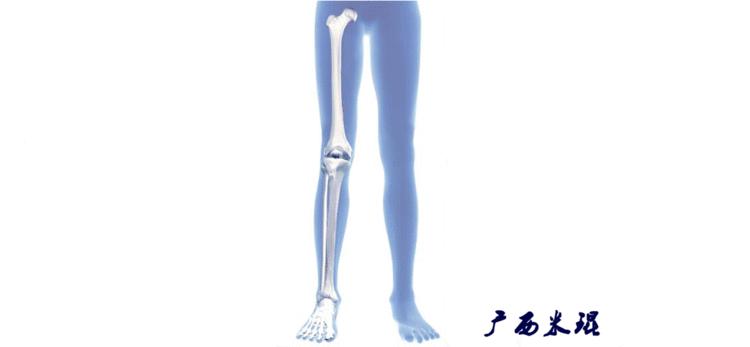

(2)机械轴

机械轴是连接近端和远端关节中心点的直线。

机械轴要分前后位及侧位,站立前后位(也就是冠状面)股骨头中心与踝关节中心的连线通过膝关节中心,这是下肢的机械轴线,也就是下肢力线,常说Mikulicz线。冠状面的力线评估在临床工作中最常用、最基础、最重要。